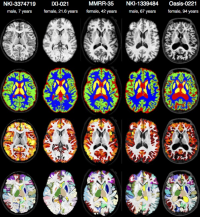

• Interdisciplinary Bachelor/Master thesis in the domain of "Atlas Generation"

ANT-2

Within this project, clinically acquired magnetic resonance imaging (MRI) brain data of the past years is processed retrospectively. Using these data the primary task is to create a brain template with the Advanced Normalization Tools (ANTs) which will serve as a reference in diagnosis in neurodegenerative and psychiatric diseases. Beyond this, further tasks may vary depending on the individual skillset and type of work.